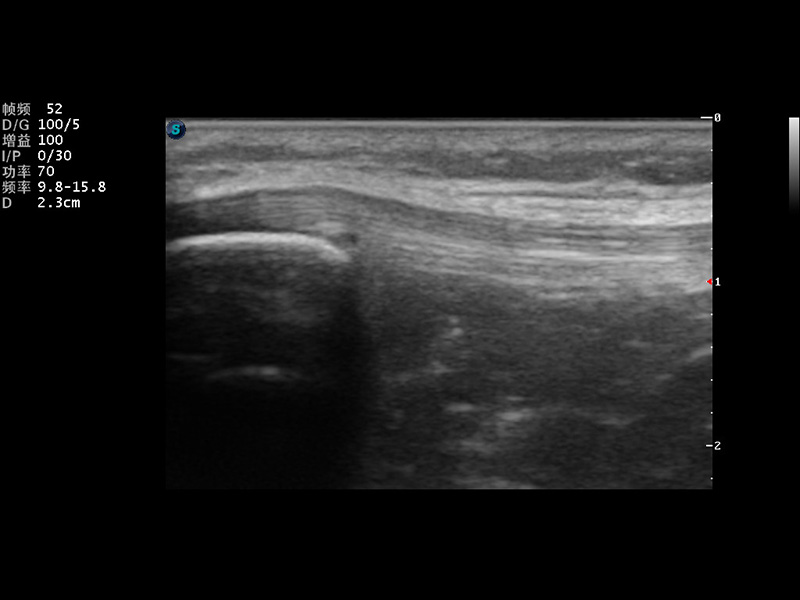

S9便携式彩色多普勒超声诊断仪是乐玩lewin国际研发的高端便携彩超设备,外观设计新颖、产品性能卓越。S9在便携超声领域采用了突破传统的触摸屏交互设计,并以先进的软件硬件技术和设计理念,为您带来清晰的图像质量、稳定的工作性能和便捷的操作体验。